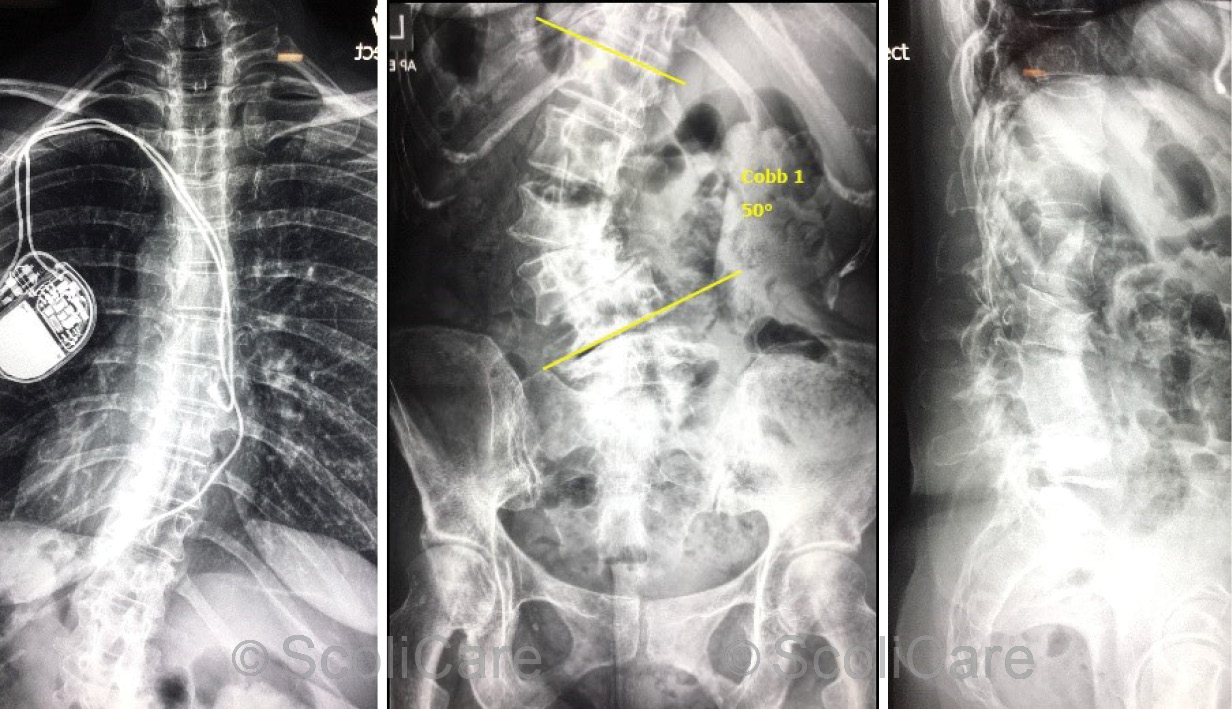

The postural improvements displayed initially in-brace have been maintained (Figure 4) and the patient’s lumbar scoliosis has remained stable at 50° (Figure 5).

Figure 5: Posteroanterior thoracic spine x-ray out-of-brace (Left), posteroanterior lumbopelvic x-ray out-of-brace highlighting a 50° left lumbar scoliosis (Middle) Lateral lumbar